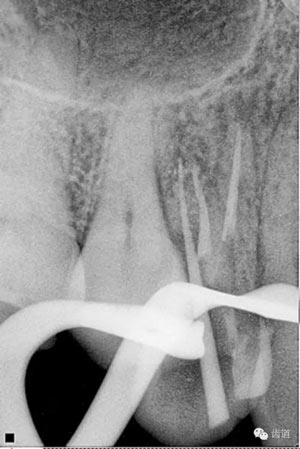

處理:放置橡皮障,去除暫封,超聲結(jié)合2%CHX清除遠(yuǎn)頰根管內(nèi)氫氧化鈣糊劑,主牙膠試合后95%酒精沖洗干燥根管,結(jié)合AH Plus糊劑連續(xù)波熱牙膠垂直加壓充填根管,樹(shù)脂分層粘接修復(fù)牙體。建議定時(shí)復(fù)診進(jìn)行嵌體修復(fù),患者未執(zhí)行。

檢查顯示:近頰及腭根充填恰填,遠(yuǎn)頰根管內(nèi)有少許充填物影像。根尖明顯低密度影像。